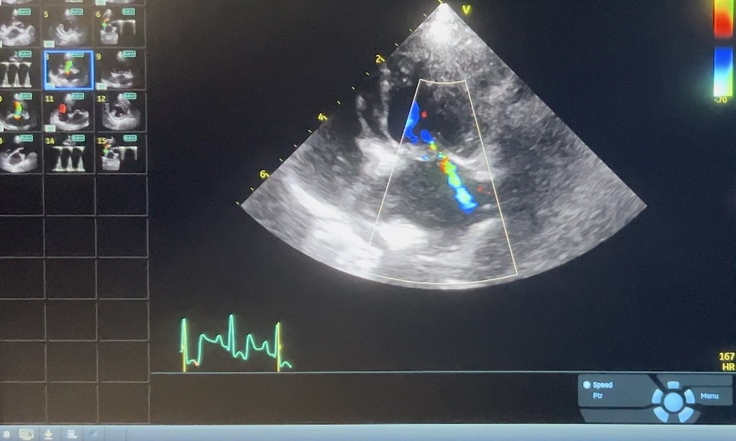

・まずは手術を済ませてほぼ正常になったワンちゃん心臓のエコーから

緑色の部分が血液の逆流です。